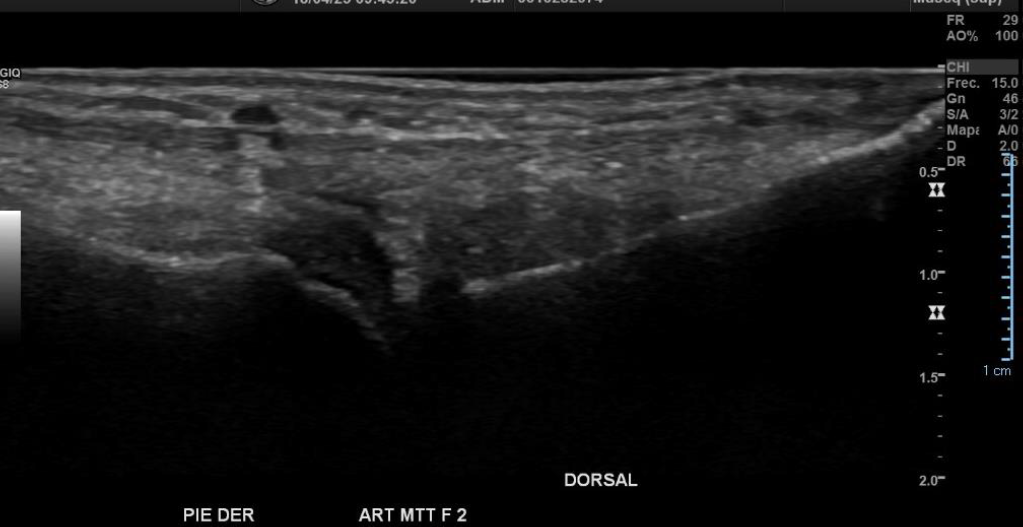

Hallazgos: Piel y tejido celular subcutáneo sin alteraciones significativas.

Engrosamiento y disminución de ecogenicidad del tendón peroneo largo en su región distal, sin desgarros.

Tendón peroneo corto, tibial anterior, extensor del hallux y extensor común de los ortejos de grosor y patrón fibrilar conservados.

Espacios articulares de amplitud normal y bordes regulares.

No hay signos de derrame articular.

Imagen con aspecto de os peroneo de contornos corticales irregulares, con cambios inflamatorios de las partes blandas adyacentes, pudiendo estar en relación a fractura a este nivel.

Impresión diagnóstica: Imagen con aspecto de os peroneo de contornos corticales irregulares, con cambios inflamatorios de las partes blandas adyacentes, pudiendo estar en relación a fractura a este nivel. Se sugiere evaluar con radiografía.

Tendinosis del peroneo largo en su región distal.